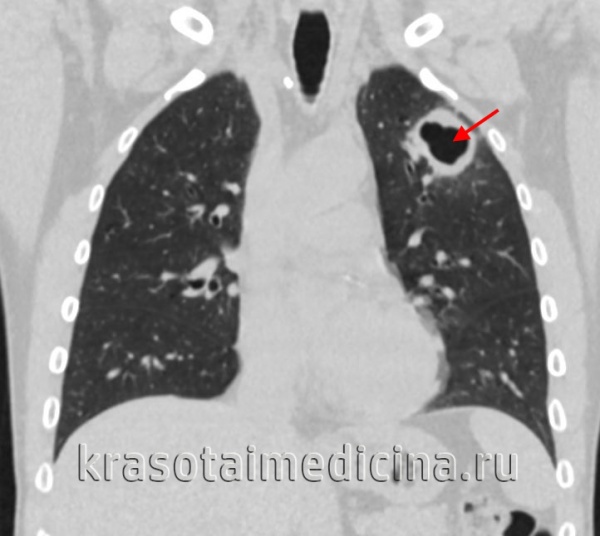

Иногда после опорожнения расплавившихся казеозных масс в лимфатическом узле формируются парабронхиальные каверны. Образование такой каверны клинически протекает иногда остро, под видом пневмонии, со значительно выраженной интоксикацией и последующим прогрессированием процесса в легких в результате аспирации большой дозы инфекционного материала. Чаще заболевание протекает хронически и волнообразно, с периодическими вспышками, с признаками затянувшегося трахеобронхита. При бронхоскопии находят большую кратерообразной формы язву, дно которой переходит в образовавшуюся полость распада. Стенка последней состоит из не полностью отторгшейся казеозно перерожденной лимфаденоидной ткани и окружающей капсулы.

В мокроте обнаруживают микобактерии туберкулеза, а при рентгенотомографическом исследовании в увеличенных внутригрудных лимфатических узлах выявляют больших или меньших размеров деструкцию, которую иногда удается заполнить контрастным веществом при селективной бронхографии (фистуло-графии).